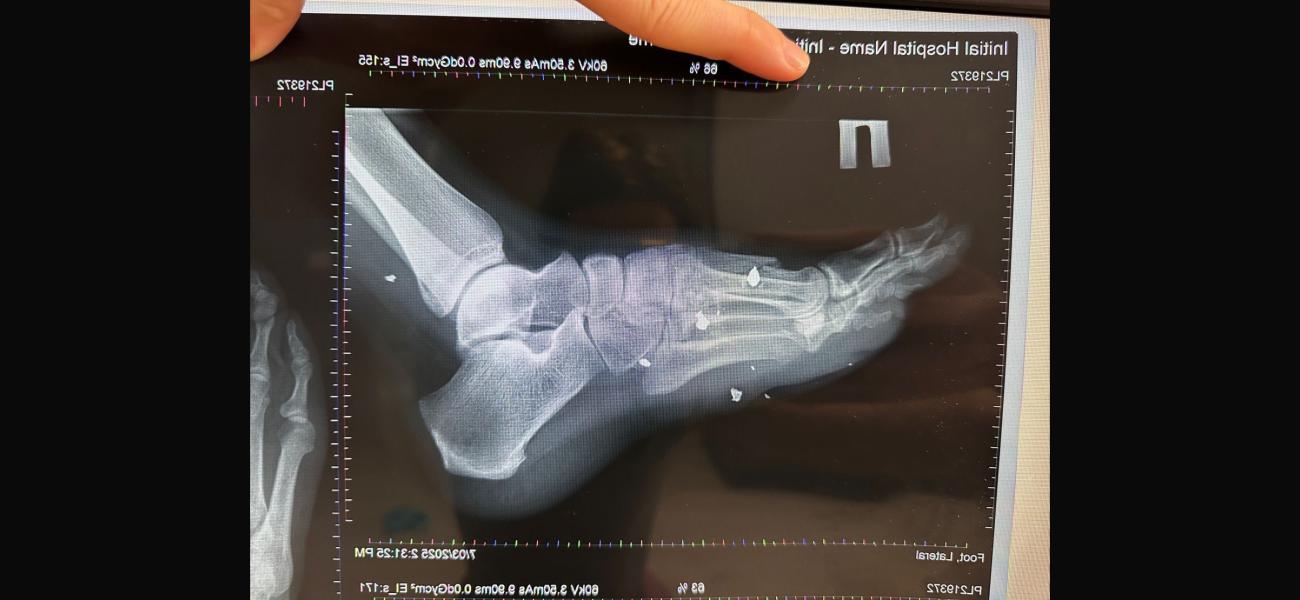

Ситуация следующая. Муж получил осколочное ранение, перелом плюсневой кости, осколок находиться в переломе прямо. Муж не чувствует 4х пальцев и не может шевелить ими. Хотя ранение было еще 22 января. К чему я, в госпитале усираются, что все само срастется и функционировать будет когда заживет, поэтому вынимать ничего не будут. Но как может срастись перелом, в котором осколок? В отпуске по ранению пытался лечь в госпиталь у нас в городе, до самого конца отпуска мурыжили что положат, ждите травматолога ( он бывает раз в сколько то дней, потому что по нескольким госпиталям бегает) когда мы наконец то 28го февраля попали к нему, он отказал в лечении. Сказал при части лечиться. Так вот хотелось бы услышать мнение врача. На случай если нам опять начнут говорить что все само пройдет.

П.с рентгены свои сделали, травматолога в частной не было в этот день, но сегодня сходим видимо просто в другую клинику, чтоб было на руках заключение. Но одно мнение специалиста хорошо, а два еще лучше